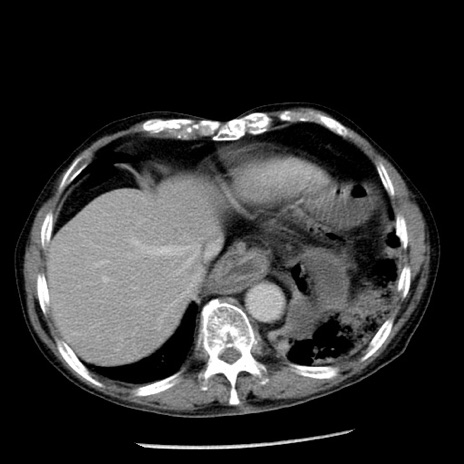

症例26(横断像)

【症例】80歳代男性

【主訴】嘔吐

【現病歴】昨晩2回嘔吐あり、今朝になっても嘔吐あり。来院。

【既往歴】胃潰瘍

【身体所見】意識清明、BT 37.6℃、BP 166/95mmHg、HR 100bpm、SpO2 97%、腹部:平坦・軟、腸蠕動音聴取良好、圧痛なし。

【データ】WBC 21900、CRP 1.46